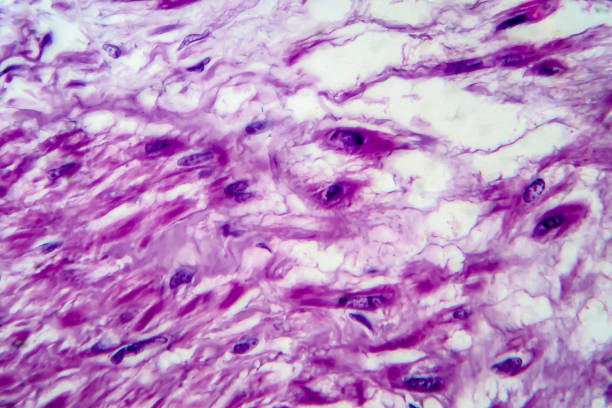

자궁근종(Uterine fibroids)은 여성의 자궁 내에 발생하는 양성 종양으로, 자궁 내막이나 근층에서 생길 수 있습니다. 대부분의 경우, 이 종양은 악성 종양이 아니며, 치료하지 않아도 괜찮은 경우가 많습니다. 그러나 증상이 심한 경우, 치료가 필요할 수 있습니다. 자궁근종의 증상은 그 크기와 위치에 따라 다릅니다. 아무런 증상이 없는 경우도 있지만, 대개는 다음과 같은 증상을 보일 수 있습니다.